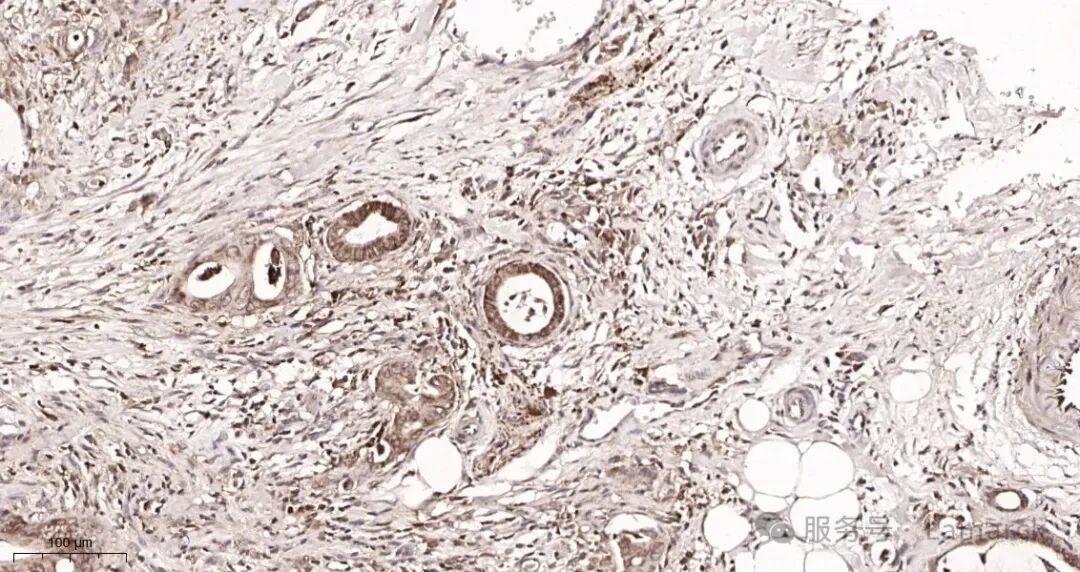

AR0025_3  Rat colon tissue.jpg

α smooth muscle actin (R356R) Rabbit mAb (AR0025)